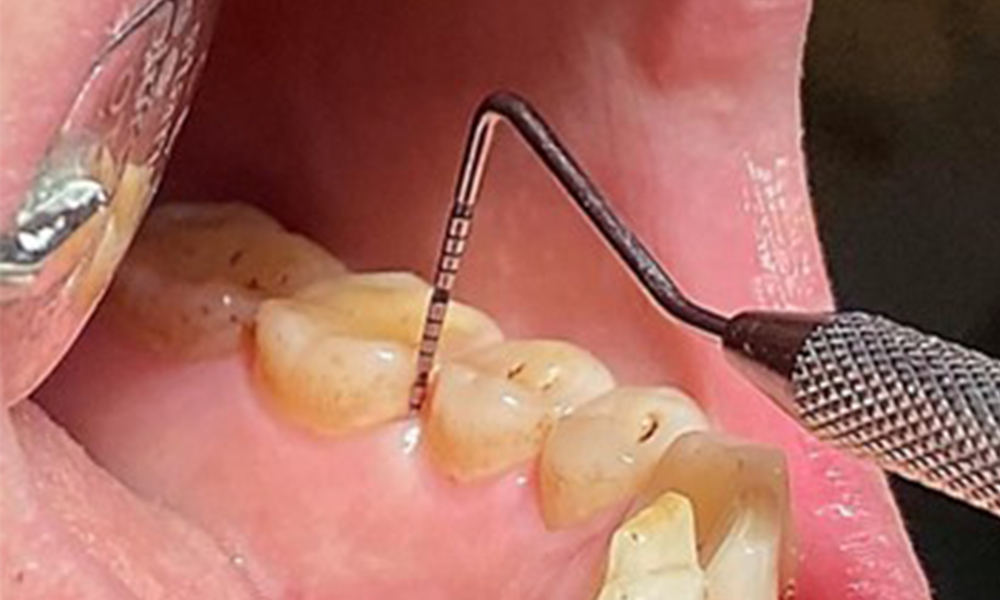

Instruction and motivation are important components of these appointments. Good home-based intraoral hygiene behaviour and understanding are important for patients. Plaque accumulation is particularly evident in the cervical regions (Fig. 8).

The arrows indicate plaque accumulations in the cervical region

Fig. 8: The arrows indicate plaque accumulations in the cervical region, © Dr R. Krapf

These must be discussed with the patient, and improvements to the teeth-brushing technique must be practised. A soft toothbrush attachment is recommended for home-based intraoral hygiene due to the presence of erosions and attritions.